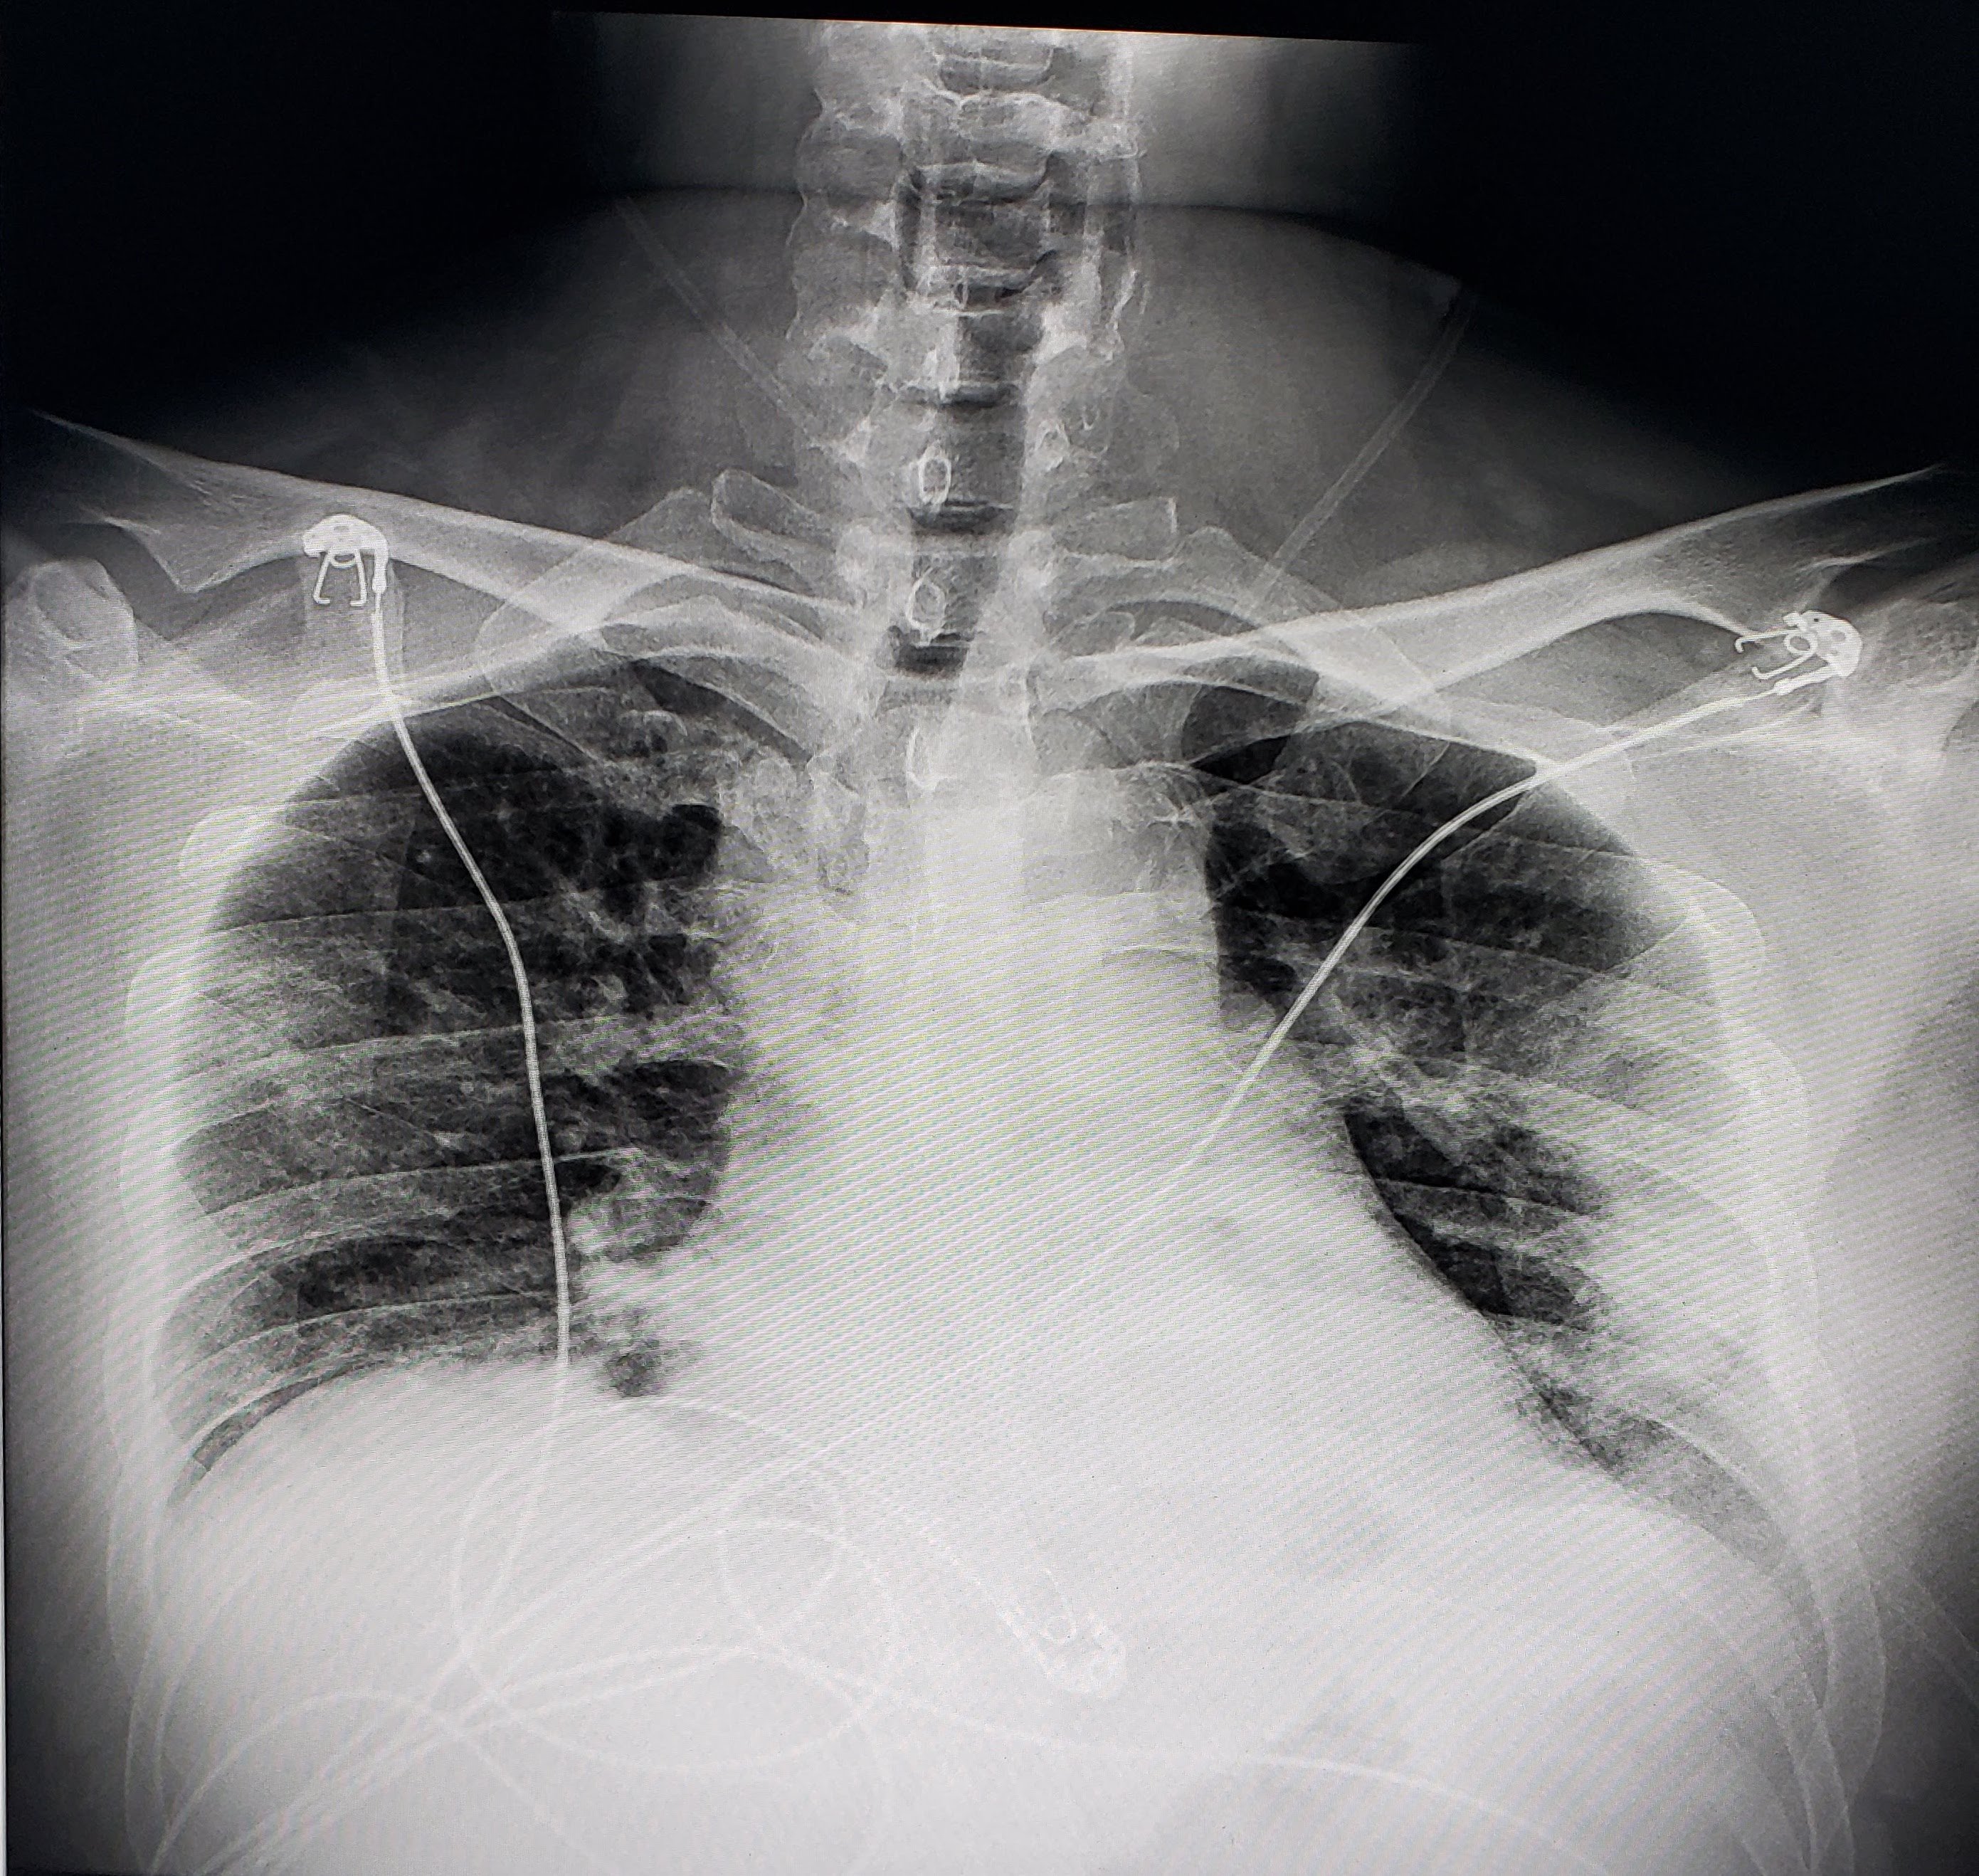

This photo gallery shows the variety of radiological presentations of COVID-19 (SARS-CoV-2) in medical imaging, including computed tomography (CT), radiograph X-rays, ultrasound, echocardiograms and magnetic resonance imaging (MRI). The radiology images show examples of typical COVID pneumonia in the lungs and the numerous complications the virus causes in the body in multiple organs, including the brain, kidneys, heart, abdomen and vascular system.

Ultrasound, especially hand-held ultrasound imaging devices, have become a primary imaging modality for novel coronavirus because of the ease to bag the device and sterilize it after use. CT and mobile X-ray systems are also used as front-line imaging systems for COVID-positive or suspected COVID patients.